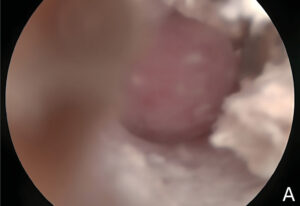

Los pólipos inflamatorios se originan en la mucosa del oído medio y, dependiendo de su patrón de crecimiento, pueden crecer hacia la nasofaringe (a través de la trompa de Eustaquio) o hacia el conducto auditivo externo (a través de la membrana timpánica) (imagen 3). La presencia de un pólipo se suele asociar con otitis media bacteriana secundaria.

La videotoscopia permite la visualización directa de los pólipos inflamatorios, que suelen estar asociados a una secreción mucopurulenta abundante en el conducto auditivo externo. Por ello, el lavado de dicho conducto es fundamental para mejorar la visualización de estas masas carnosas y facilitar su diagnóstico.